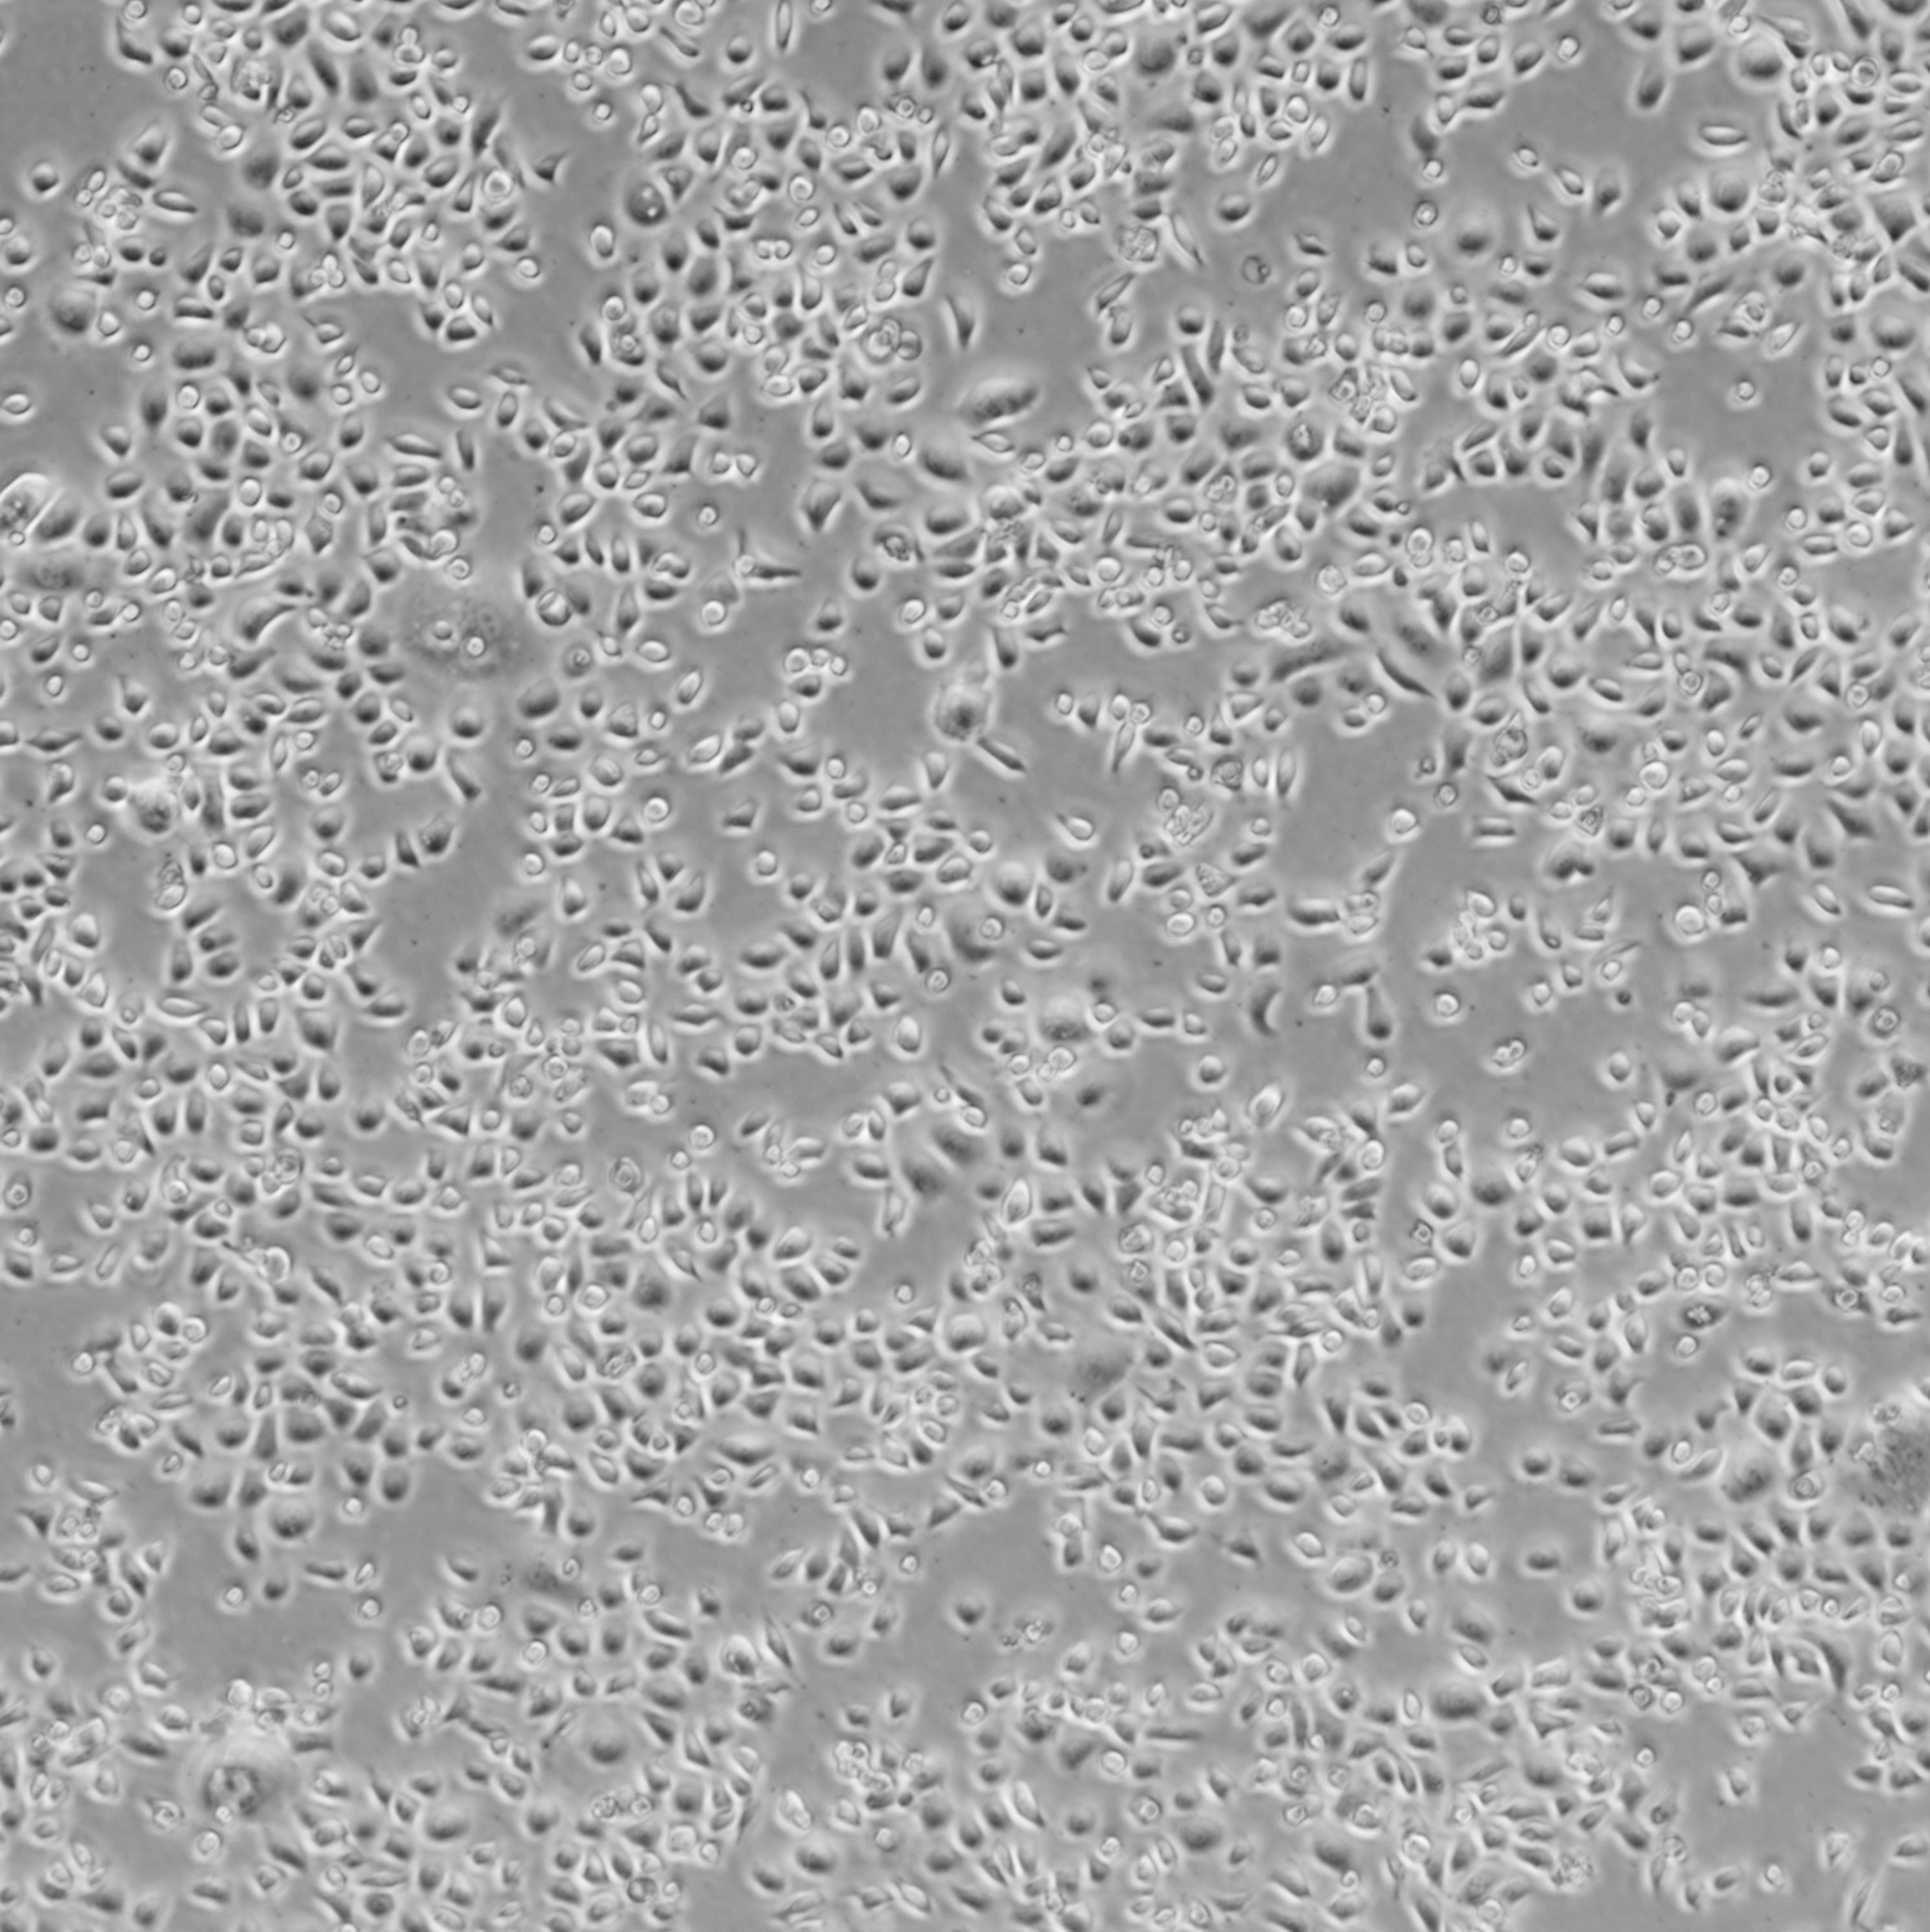

ME-180_人表皮样癌细胞

细胞名称:ME-180_人表皮样癌细胞

货号: SNB-TC-1239

种属来源:人

性别年龄:女性,66岁

组织来源:子宫

生长特性:贴壁生长

细胞形态:上皮样

细胞规格:1 X 106cells/T25或1 mL冻存管

培养条件:McCoy's 5a Medium + 10% fetal bovine serum (FBS)

37 ℃, 5% CO2